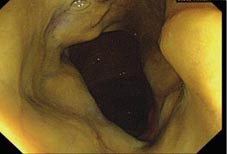

一位37歲男性過去曾因三酸甘油脂過高引發壞死性胰臟炎而接受腹腔內膿瘍引流術及長期抗生素治療,這次因糖尿病控制不佳引發糖尿病酮症酸中毒(Diabetic Ketoacidosis, DKA)住院,住院期間因克雷伯氏肺炎菌(Klebsiella Pneumoniae)菌血症接受靜脈注射第三代頭孢菌素抗生素14天,期間發生嚴重的持續性腹瀉,大腸鏡發現偽膜性大腸炎(Pseudomembranous Colitis)(如:圖一,大腸黏膜被厚厚一層黃色滲出物包覆)。給予口服抗生素甲嘧唑乙醇 (Metronidazole)一星期後並無明顯改善,於是給予後線的口服抗生素萬古黴素 (Vancomycin) 一星期後腹瀉才獲得緩解。

圖一、大腸黏膜被厚厚一層黃色滲出物包覆